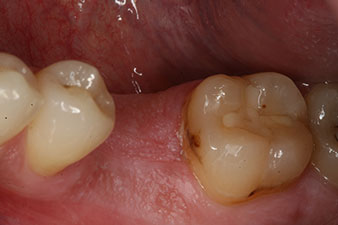

Fig. 2: Six weeks later there was an incompletely ossified alveolus in the region of the mesial root.

However, six weeks after the extraction incomplete ossification was found after preparation of the mucoperiosteal flap in the region of the former mesial alveolus.